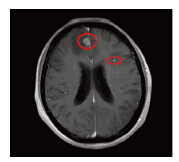

病例1:患者,女,60岁,因发现左乳肿块2月,于2011年8月12日在我院行全麻下左乳肿块切除术+术中快速病检+左侧全乳切除术+左腋窝淋巴结清扫术,术后病检示:左乳浸润性导管癌Ⅱ级(肿瘤大小约1.5 cm×2.3 cm),脉管内可见癌栓,左腋窝淋巴结10/24枚可见转移癌,ER(2+),PR(-),HER2(3+)。诊断:左乳浸润性导管癌,pT2N3M0期。术后行多西他赛(75 mg/m2)+吡柔比星(50 mg/m2)3周方案,化疗6周期。化疗后行左胸壁和左锁骨上区域放射治疗,处方剂量为50 Gy/25次。未行靶向治疗。随后行芳香化酶抑制剂内分泌治疗(阿那曲唑,1 mg,口服,每日1次)。于2012年6月因剧烈头部疼痛入院,入院行颅脑MRI示:脑部多发转移瘤,见图 1。测肿瘤标志物正常,同时行全身体检,包括胸片、彩超、全身骨扫描等未发现其他远处转移。行脱水,降低颅内压治疗,同时行颅脑调强放射治疗,其中全脑预防照射剂量40 Gy,转移灶局部放射剂量增至60 Gy。但因病情进展迅速,于2012年7月死亡。

| Red circle marks indicated the two metastatic lesions 图 1 病例1脑转移MRI Figure 1 The MRI of brain metastases in the first patient |